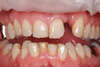

4- les implants en remplacement de dents infectées

Les dents portant un bridge ancien se sont infectées

Après extraction, deux implants et une prothèse provisoire implanto portée sont installés

Après une phase de cicatrisation de 4 mois, le bridge définitif peut-être réalisé